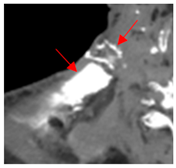

| 2 | 0–25 | 1564 | ![]() Axial CT image shows a partly necrotic tumor in the right neck. | ![]() Axial CT image obtained 18 days after injection shows the NBTXR3 nanoparticles (arrows) in the tumor. |